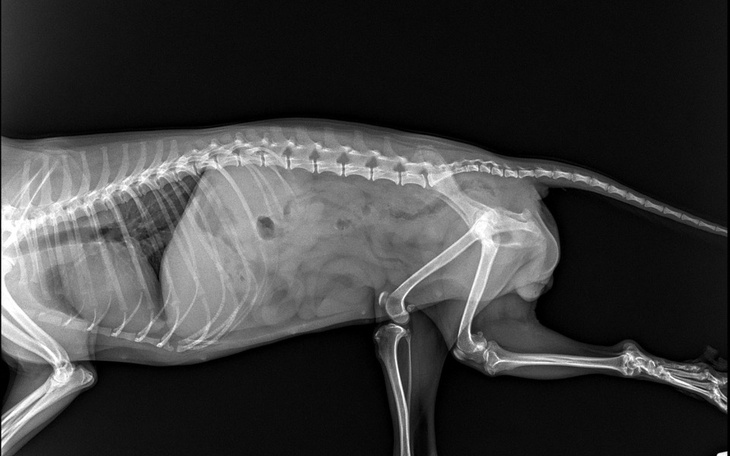

Zwracam się do Was z prośbą o pomoc dla naszego wspaniałego, czterołapego przyjaciela, który w tych trudnych chwilach potrzebuje naszej miłości i wsparcia. Nasz ukochany pies, Molly zmaga się z poważną chorobą – dysplazją stawu biodrowego. Jest to bolesna dolegliwość, która ogranicza jego ruchy i sprawia, że każdy krok to dla niego ogromny wysiłek.

Leczenie dysplazji stawu biodrowego jest kosztowne. Potrzebujemy zebrać 6 tysięcy złotych na operację i rehabilitację, która przywróci Molly zdrowie i sprawność. Każda, nawet najmniejsza wpłata, jest dla nas na wagę złota i przybliża nas do celu, jakim jest uratowanie naszego psa od cierpienia.